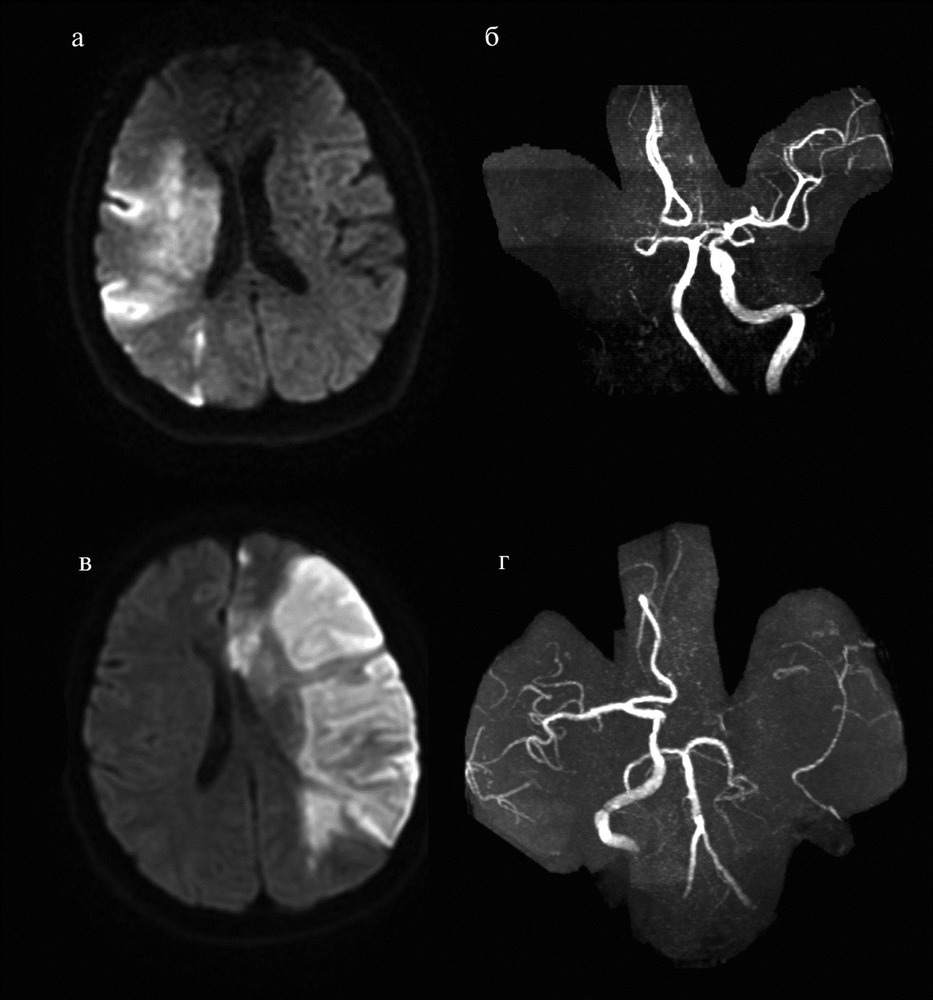

Ишемический инсульт левой стороны: симптомы и реабилитация